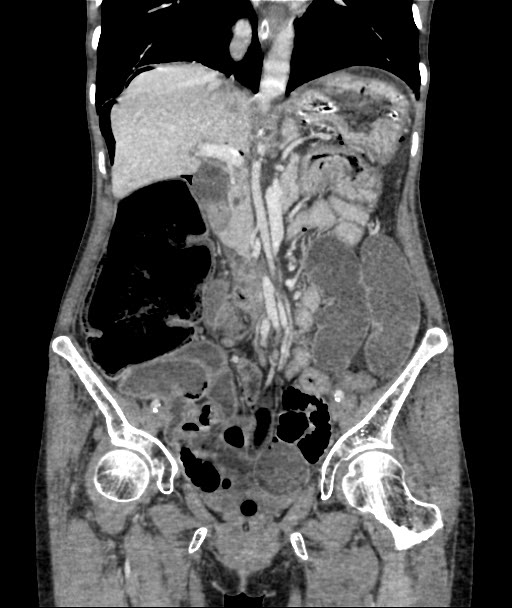

CECT Abdomen: F/S/O Acute Intestinal Obstruction (transition point in transverse colon) with minimal free fluid in pelvis with pneumoperitonium with few air foci in the wall of ascending colon Pneumatosis intestinalis

Cause Midgut volvulus

Adhesion Band

Figure 2: Cect Showing Features of Intestinal Obstruction

Radiologic imaging may be abnormal and detect CV in 45–56% of the cases [5] .Plain abdominal x-ray is highly sensitive for the diagnosis of CV with the characteristic “coffee bean“ sign deformity, its apex pointing to the left upper quadrant [9]. Other findings commonly seen are cecal dilatation (98−100%), single air–fluid level (72–88%), small bowel dilatation (42–55%), and absence of gas in the distal colon (82%). CT is more sensitive and specific for diagnosing CV and detecting complications [10].